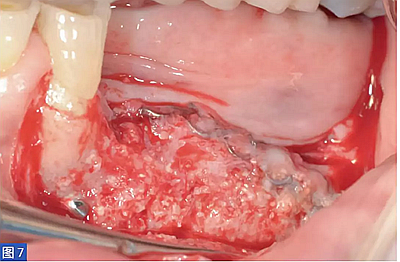

圖8:病例1. 術(shù)后6 個月的再生組織。咬合面觀。